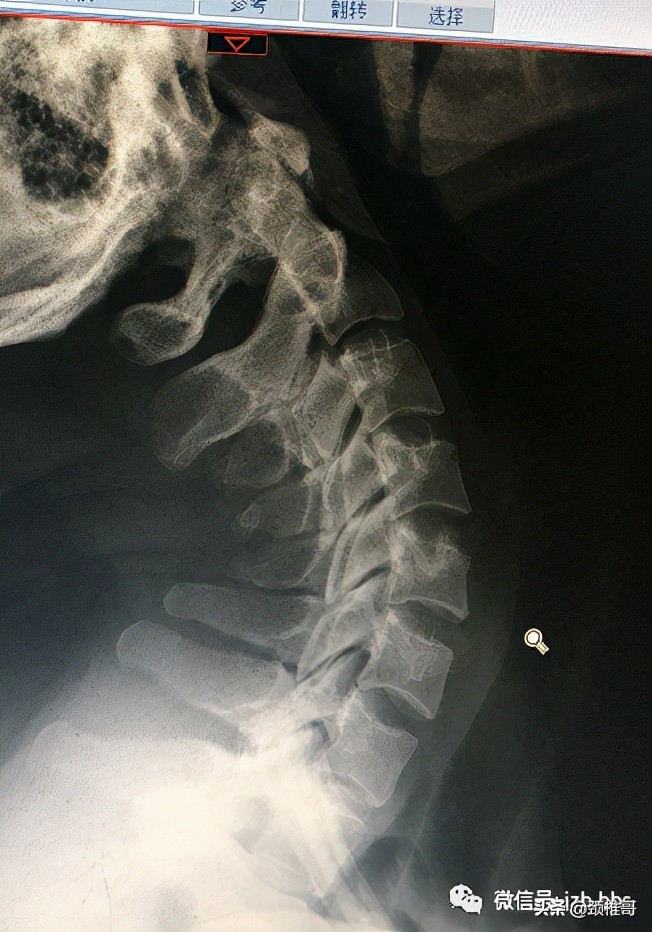

#颈3一7椎骨质增生该怎么办#

脖子细长,关节松弛, 4-5夹角大于11度不稳的表现